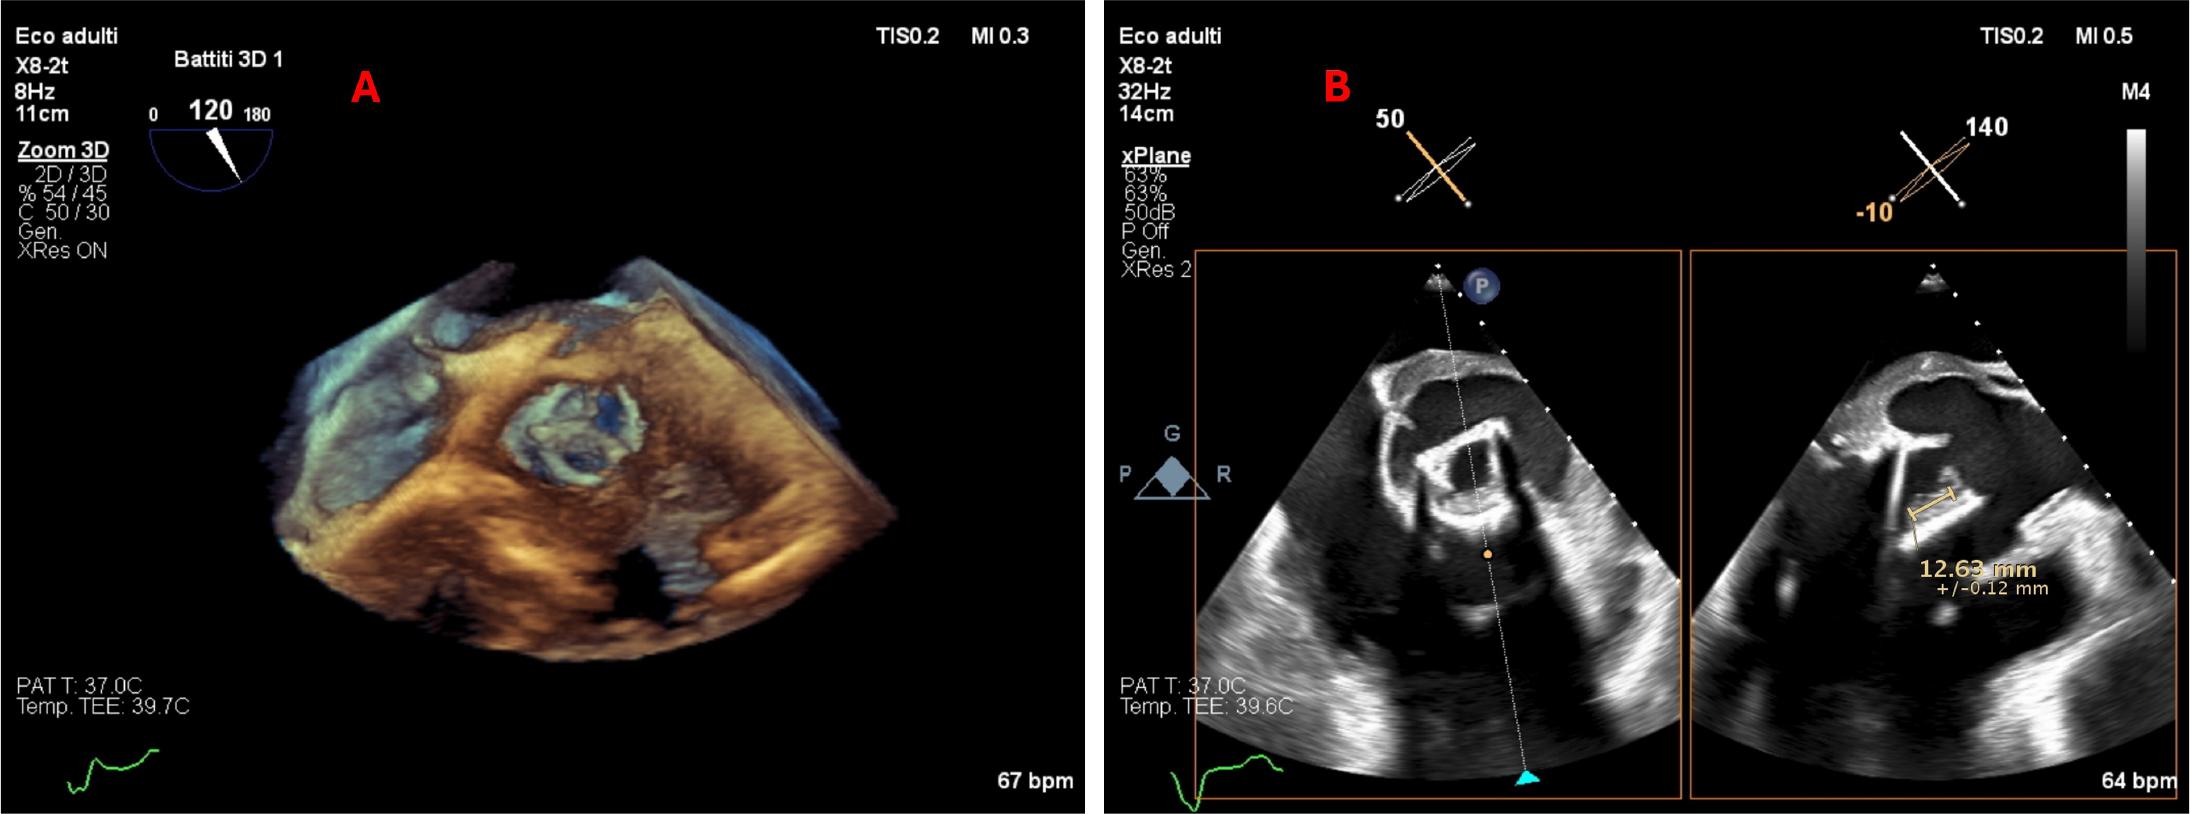

Figure 1